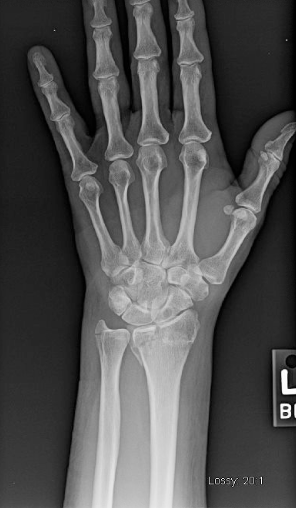

Big Bad: DRUJ dislocation with ulnar styloid process fracture

Big Bad: DRUJ dislocation with ulnar styloid process fracture from 3.bp.blogspot.com

S62.0 fracture of navicular scaphoid bone of wrist. International statistical classification of diseases and related health problems 10th revision. To code a diagnosis of this type, you must use one of the seven child codes of s62 that describes the diagnosis 'fracture at wrist and hand level' in more detail. M84.561a pathological fracture in neoplastic disease, right tibia c40.21 malignant neoplasm of long bones of right lower limb. There is a transverse fracture of the distal left radius just proximal to the wrist joint with. At this time, the healing process will have started in the bone, which will help the fracture site to show up. Assessment of a wrist fracture must also include a description of the distal ulna and distal radioulnar joint (9). Learn vocabulary, terms and more with flashcards, games and other study tools. Bila anda menggunakan desktop (laptop) silahkan tekan ctrl + f. S62.0 fracture of navicular scaphoid bone of wrist. Unspecified fracture of wrist and hand. Fracture of distal parts of ulna and radius (s52. Although a broken wrist can happen in any of these 10 bones, by far the most common bone to break is the radius. The reduction was unsuccessful, because there is a dorsal tilt > 10 degrees , loss of inclination and radial. More information on how to use the online browser is available in the help. This is called a distal radius fracture by hand surgeons (figure 1). Shoulder, wrist, hand, foot, toes subsequent encounter for fracture w/ routine healing.